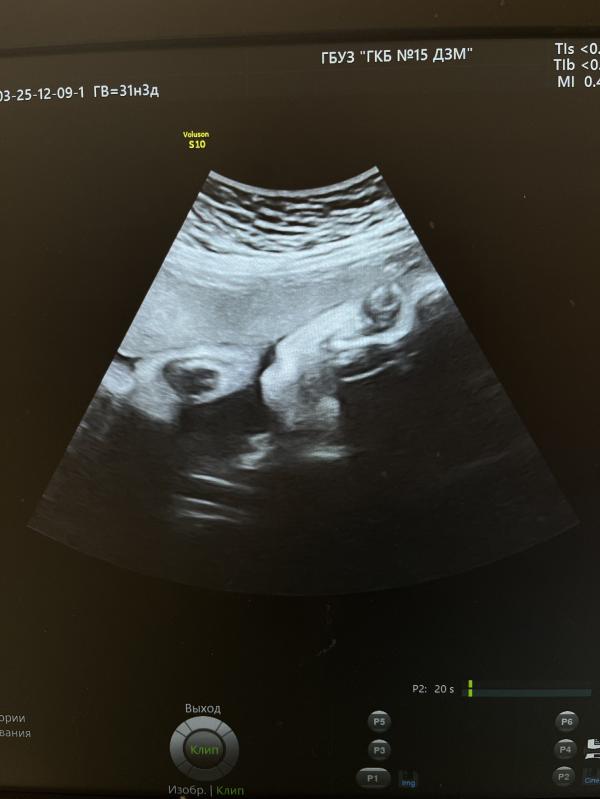

3 скрининг пройден

Вес 1755 +/- 256 гр

ЧСС 150 уд. в минуту

На 9 см выше внутреннего зева

Если еще почитать протокол УЗИ врача, то она пишет «В продольном положении в головном предлежании» и про пуповину «петель достаточное количество»